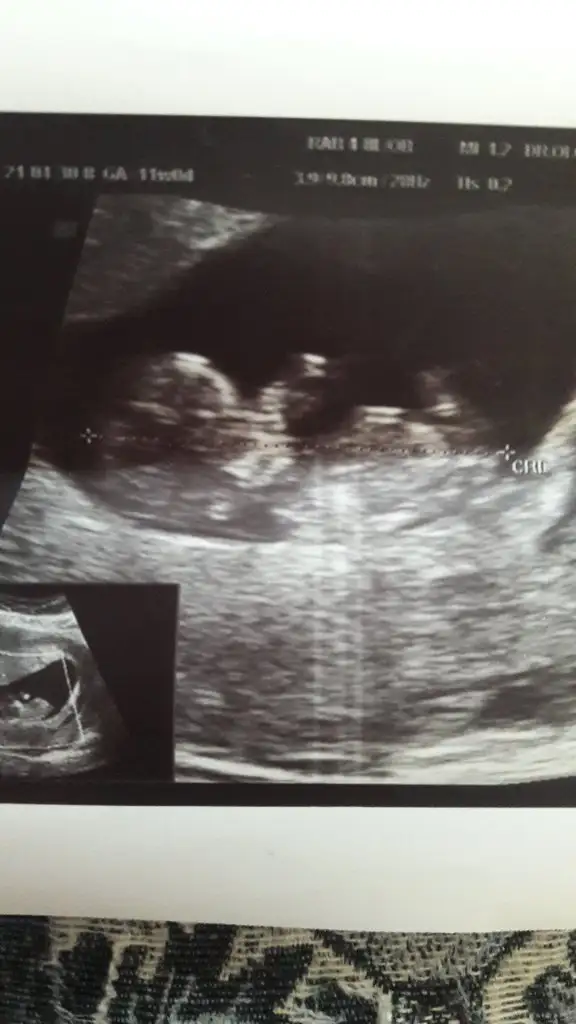

14+3 tahminde bulunurmusunuz🤦‍♂️

• USER_SCOPED_TEMP_DATA_MSGR_PHOTO_FOR_UPLOAD_1619699855146_6793513581238554568.webp

USER_SCOPED_TEMP_DATA_MSGR_PHOTO_FOR_UPLOAD_1619699855146_6793513581238554568.webp

16,7 KB · Görüntüleme: 69

• USER_SCOPED_TEMP_DATA_MSGR_PHOTO_FOR_UPLOAD_1619699207153_6793510863365994738.webp

USER_SCOPED_TEMP_DATA_MSGR_PHOTO_FOR_UPLOAD_1619699207153_6793510863365994738.webp

24,1 KB · Görüntüleme: 67